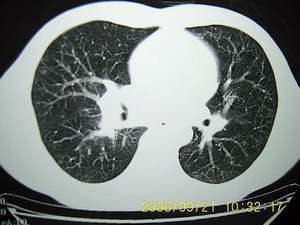

男 27岁 咳嗽一个月,治疗无效。

右肺下叶后段及右肺门附近见斑片状模糊影,密度不均,部分实变,右肺门附近见肿大淋巴结影.

两肺弥漫均匀分部粟粒壮影 右肺基底段不规则软组织密度影其内密度不均 纵隔内淋巴结钟大 请进一步右肺病灶薄层检查及补充病史后再会诊

右肺下叶后基底段结节样病灶,边界不规则,密度不均,右肺门团片影,肺门增大,纵隔见肿大淋巴结.结合临床首先考虑:肺结核.

图像显示:右下肺门增大,伴右下肺斑片状高密度影,密度不均;右下肺支气管管壁增厚,纵隔内淋巴结肿大。意见:支气管内膜结核、结节病。建议行纤支镜检查。

右下肺脊柱旁结节样肿块,可见毛刺,右侧肺门影增大,并见气管隆突前、主动脉窗内多发结节影。

临床无明显发热,男 27岁 咳嗽一个月,治疗无效。

考虑青年人周围型肺癌并右肺门、纵隔淋巴结转移。

右肺门影增大,纵隔内可见多个淋巴结肿大,右肺下叶内后基底段斑片状模糊影,两肺间质性改变;考虑右肺内结核并右肺门及纵隔淋巴结结核可能性大;职业病及结节病待排;肿瘤不太支持,年龄轻,无咯血,未见明显支气管狭窄,建议穿刺活检。

右肺门阴影增大,见有钙化,右肺下叶后基底段片状影,结合治疗史考虑右肺下叶结核

m 27 右肺门影增大,纵隔内可见多个淋巴结肿大,右肺下叶内后基底段斑片状模糊影,两肺间质性改变;考虑结节病或结核,建议纤维支气管镜穿刺活检.鉴别诊断1;淋巴瘤,纵隔淋巴肿大(胸骨后淋巴肿大突出)进展快,范围不够大,无融合及包埋改变..2结核其淋巴结密度是不均匀的,其内部一般有干酪坏死.可有钙化.可做ppd试验进一步明确.3结节病往往表现为肺门淋巴结对称性肿大.